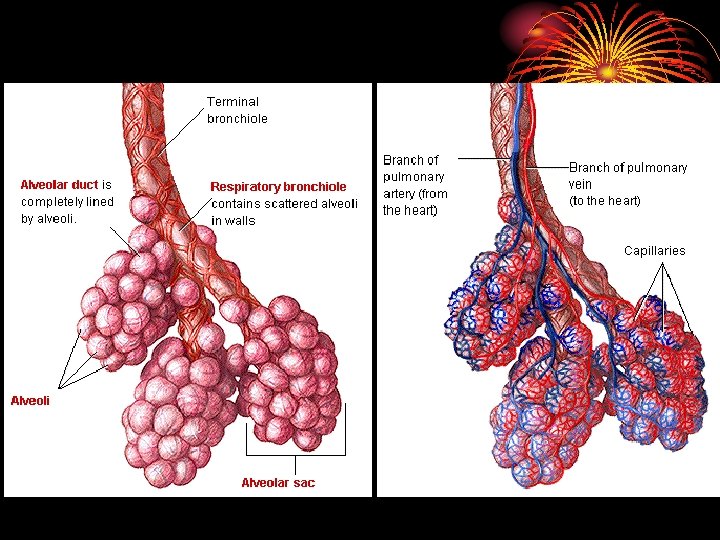

ANATOMY • Right lung three lobes and left two. • Each lobe divided into segments. • Trachea divides into main two bronchi then bronchioles, terminal b. and respiratory b. reaching the alveolar ducts to the alveoli. • Between the trachea and the alveoli airways divide 23 times, 16 conducting & 7 from resp. b. involved in gas exchange.

• area from 2. 5 cm 2 (trachea) to 11800 cm 2 in alveoli ? Air velocity. • 300 million alveoli, 70 m 2. • Alveoli lined by type 1 cells ( flat lining ) and type 11 cells ( granular pneumocytes secrete surfuctant ). • Pleura. • Respiratory muscles.